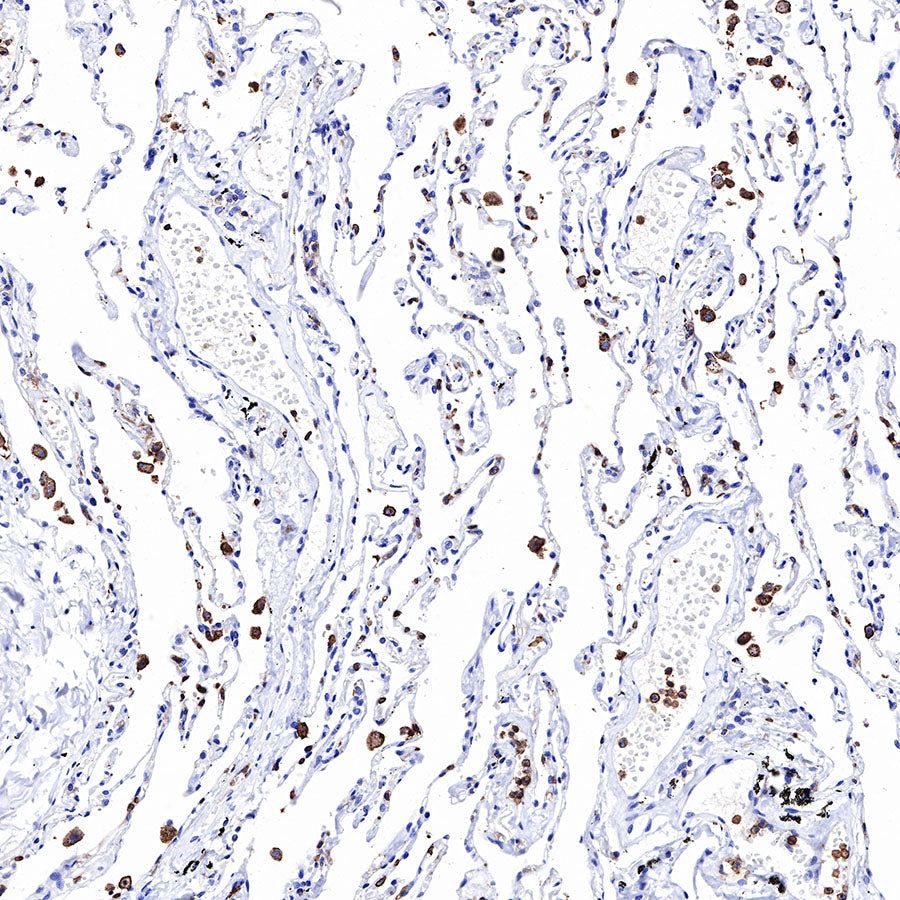

IHC shows positive staining in paraffin-embedded human lung. Anti-CD43 antibody was used at 1/1000 dilution, followed by a HRP Polymer for Mouse & Rabbit IgG (ready to use). Counterstained with hematoxylin. Heat mediated antigen retrieval with Tris/EDTA buffer pH9.0 was performed before commencing with IHC staining protocol.